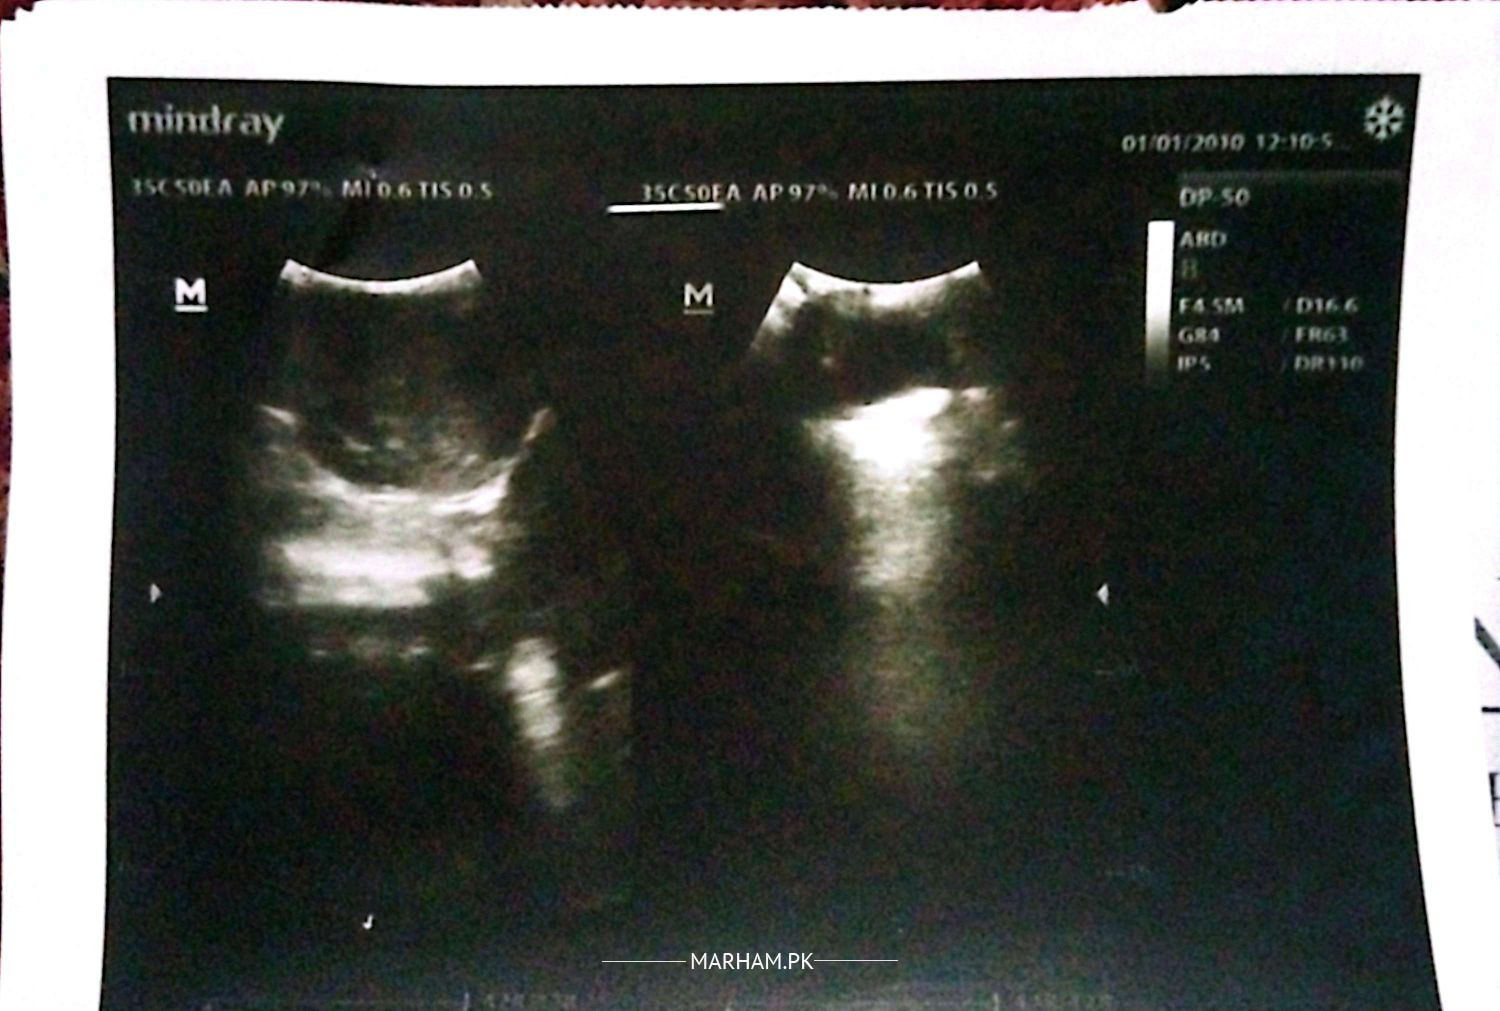

My daughter is one month old. She passed meconium at the time of delivery; however, since then, she has not been able to pass stool on her own. She only passes stool when a glycerin suppository is inserted; otherwise, she does not. We have consulted a doctor, who advised an X-ray, and an ultrasound was also performed. According to the ultrasound report, everything appears normal. Despite this, I am concerned about why she is unable to pass stool independently. Kindly guide me on what steps I should take?

kindly see a paediatrician and paediatric surgeon for a full assessment. there seems to be gaseous distention with decreased air in rectum/pelvic region. also don't make a habit of giving suppositories, motherfeed two hourly

we have consulted a pediatrician.he has prescribed ezigut drops,dromax,skilax drops.it has been 5 days that i am giving her these medicines but still she is not passing stool by her own.i have attached ultrasound report alongwith my post